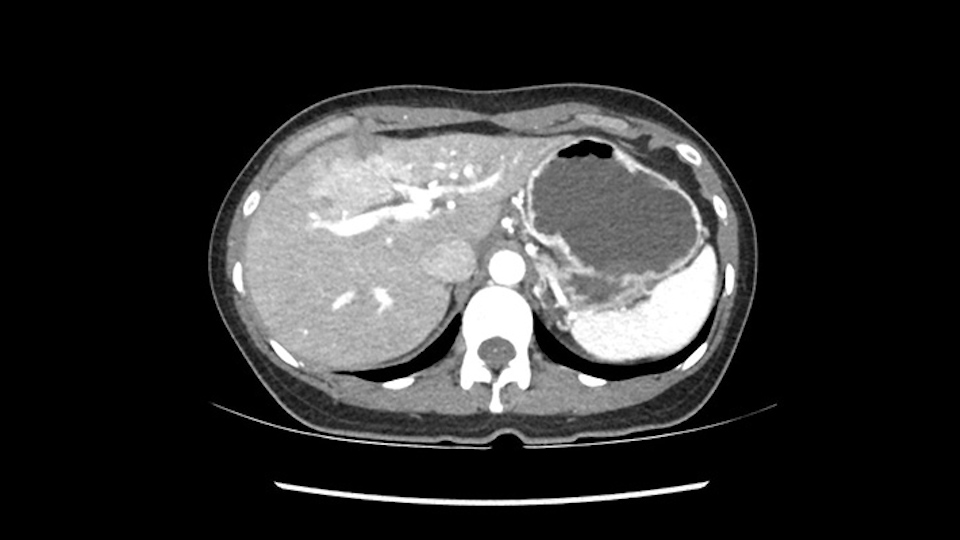

So if we look at the CT scan, on the axial, it’s a larger lesion. It’s about 6 or 7 or 8 centimeters. So it does look a bit threatening in terms of its resectability but if you really drill down deeply into the anatomy, and I think the coronal [imaging] is even better, you can see that the entire mass is on the patient’s left side of the falciform ligament. So it’s really only a left-sided tumor and not even really a left-sided tumor because Segment 4 is uninvolved anatomically.

As I review the CT scan, we have both arterial and venous phases, the tumor is obvious. But I’ll start by saying that the liver itself does not appear to be cirrhotic to my eye. It’s got a normal contour and allied to that, that I do not see evidence of portal hypertension. The spleen is normal, there’s no collateral vessels. The tumor itself, I measured maximally at about 11 centimetres in diameter and I’m told the alpha fetoprotein is very high (over 10000), which is entirely consistent with this being a solitary hepatocellular carcinoma that is very exophytic. It seems to emanate off the inferior margin of Segment 3 (because that’s the falciform). I’ll start by saying that this is not transplantable. The tumor exceeds our guidelines for transplantation, but it's likely resectable based on normal liver and no portal hypertension.

When you see the axial sections of the scan, you find it's a largely exophytic mass and its well-encapsulated. So this is typically true of a well-differentiated hepatocellular carcinoma. If you look at this, this is the gallbladder which is being displaced to the right and the mass is in the Sg4 of the liver, exophytic, projecting down. As it is coming down, it is also displacing the duodenum and the head of the pancreas which is being pushed towards the left and it's going right up to the cava, the start of the anterior surface of the cava. Obviously getting a lot of collaterals and vascularity from all the vessels around but one has to be very careful in evaluation of the main portal pedicle in this particular case and of course arterial inflow to the Sg4 and of course the left lobe of the liver.

So in planning for this operation, as I look at the scans, I first visualize the arterial phase and I can see that there’s are a lot of big feeding arteries to this large tumor. Likely all the right side vessels feeding the right side of the liver: right hepatic artery and likely the Segment 4 artery are spared from the tumor. It’s likely the left hepatic artery is ramificating and giving feeding arteries to this tumor. It certainly looks like a large mass that its compressing other structures like the cava, the pancreas, the stomach; but I think there’s a plane and we can see that better in the venous phase. There’s a plane of separation between the gallbladder, the pancreas, the cava, that this tumor is abrupting but likely not invading. Usually, these masses actually don’t invade at that level and basically are pushing the tissues and once you open, you’re able to separate the tumor. Sometimes there’s some adhesions but you can actually separate and there’s usually no invasion.